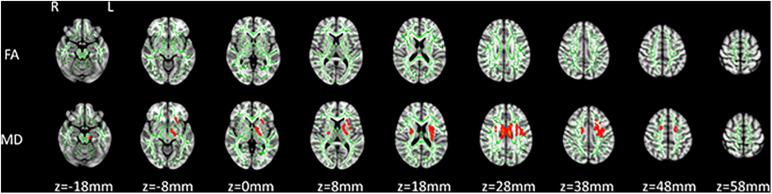

Neither carriers nor non-carriers developed any neurological symptoms during 2 years of follow-up. Baseline analysis showed no differences between the carrier and non-carrier groups in MD and FA. Follow-up analysis showed significantly increased MD in multiple WM tracts, among which increased MD in the bilateral superior longitudinal fasciculus, bilateral anterior thalamic radiation, bilateral cingulate gyrus, and left uncinate fasciculus overlapped the patterns observed in patients with symptomatic CJD.

在2年的随访期间,携带者和非携带者均未出现任何神经系统症状。基线分析显示,携带者组和非携带者组在MD和FA方面没有差异。随访分析显示,多个白质束中的MD显著增加,其中双侧上纵束、双侧丘脑前辐射、双侧扣带回和左侧钩束中MD的增加与有症状CJD患者中观察到的模式重叠。